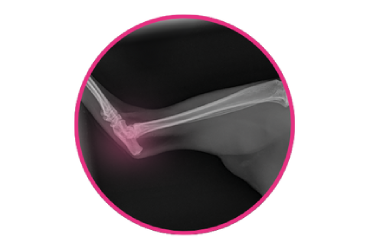

From bandages and pain relief to life-saving fluids and breathing tubes, our emergency kits are vital for treating pets in critical conditions. Life-saving operations need to take place every day, and we urgently need more emergency equipment to save pets in these crisis situations.